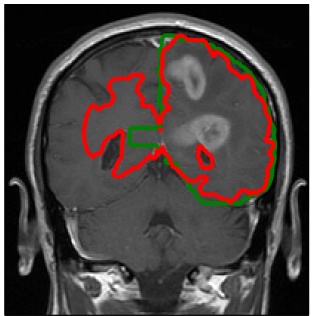

Refer to caption

Figure 4: Comparison of manually defined targets (light/dark green) and model derived targets (orange/red). In the clinical treatment plan, the light green volume was prescribed to 60 Gy, the dark green volume to 46 Gy. The yellow contour shows the abnormality on T2-FLAIR.

3.1 Target volume definition

Figure 4 shows the clinical target volume (dark green contour) and the boost volume (green contour) drawn manually by the physician, i.e. these contours were the basis for the treatment plan that was actually delivered to the patient. The prescribed dose to the boost volume was 60 Gy, the prescribed dose to the CTV was 46 Gy. The boost volume is defined based on a 2 cm isotropic extension of the contrast enhancing lesion. The CTV is defined via a 1.5 cm expansion of the T2-FLAIR abnormality. Both volumes were subsequently trimmed manually to account for anatomical boundaries (dura, ventricles, falx, and tentorium cerebelli). The dose distribution of the 3D conformal treatment plan delivered to the patient is shown in figure 6d.

Using the tumor growth model, the target volume can be defined as an isoline of the tumor cell density. This is illustrated here for the tumor cell density shown in figure 3a obtained for the parameter value Dw/Dg=100subscript𝐷𝑤subscript𝐷𝑔100D_{w}/D_{g}=100. The red and the orange contours in figure 4 show the CTV and the boost volume derived from the tumor growth model, respectively. In this example, the target defining isolines are chosen such that the total enclosed volume is equal to the manually delineated target. In the following two subsections, we discuss the differences between manual and model-derived target volumes in detail.

In the manual delineation of the CTV used in the clinical plan, it is incorporated that the falx represents an anatomical barrier for the migration of tumor cells. Hence, the isotropic target expansion was trimmed manually. In the tumor growth model, the falx is modeled via a layer of CSF and is automatically accounted for through the assumption that tumor cells only migrate within white and gray matter. However, the corpus callosum connects the two hemispheres of the brain. The tumor growth model describes the migration of tumor cells through the corpus callosum (see figure 3 and 5a). As a consequence, the target volume based on the growth model is extended into the contralateral hemisphere. Figure 5a shows the tumor cell density overlaid on the coronal T1 gadolinium image. This illustrates the three-dimensional modeling of tumor spread via the model, including areas superior to the corpus callosum. This is not consistently accounted for in the manual CTV. In the manually drawn target volumes, the target is slightly extended into the contralateral hemisphere on the slices that show the corpus callosum, but not on the slices located superiorly and inferiorly (figure 5b). In the model derived target volumes, the target is extended further into the contralateral hemisphere, and the spread of tumor cells in superior-inferior direction beyond the corpus callosum is modeled.